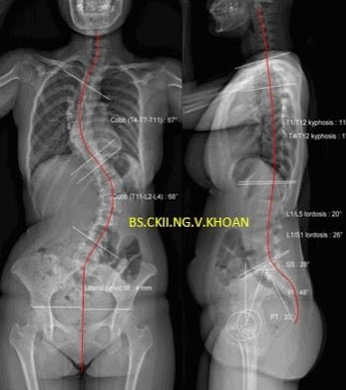

Bệnh nhân được cho chụp X-quang cột sống từ cổ đến khung chậu thẳng và nghiêng để đo độ Cong vẹo cột sống (đo góc Cobb, góc còng lưng, góc ưỡn thắt lưng). Chụp X-quang tư thế nghiêng trái và phải tối đa để dự đoán độ mềm dẻo của cột sống. Nếu phát hiện có các dấu hiệu tổn thương thần kinh, tủy sống, bác sĩ sẽ chỉ định chụp cộng hưởng từ để đánh giá các tổn thương liên quan đến vẹo cột sống.

- Vẹo cột sống vô căn tuổi thành niên (adolescent idiopathic scoliosis): Là thể vẹo cột sống thường gặp nhất. Nếu vẹo nhẹ có thể theo dõi và chụp X-quang định kỳ, do góc vẹo (góc Cobb) để so sánh tiến triển. Nếu góc vẹo vẫn dưới 25 độ, không cần điều trị gì thêm. Tái khám khoảng 3-4 tháng 1 lần để xem vẹo có nặng thêm không? Chụp X-quang định kỳ và đo góc vẹo mỗi năm. Nếu góc vẹo trong khoảng từ 25-40 độ và bệnh nhân còn trong giai đoạn tăng trưởng chiều cao, có thể cho mang nẹp thân. Nếu bệnh nhân đã hết tăng trưởng chiều cao thì không cần mang nẹp thân nữa. Trường hợp góc vẹo trên 40 độ, cần mổ nắn chỉnh.